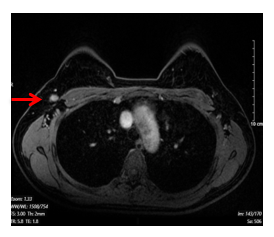

– Chụp cộng hưởng từ tuyến vú hai bên: (03/07/2024)

- Vú Phải:

- Vị trí góc ¼ trên trong có khối kích thước 25x61mm, tăng tín hiệu trên STIR, hạn chế khuếch tán trên DWI/ADC, sau tiêm ngấm thuốc sớm, tăng dần, không thấy thải thuốc.

- Không thấy hình ảnh tụt núm vú, không thấy co kéo da

- Hạch hố nách bên phải, chặng I có vài hạch, có vỏ dày, kích thước lớn nhất 7x13mm

- Vú trái: Hệ thống ống tuyến cân đối, không thấy khối, không tụt núm vú, không co kéo da

Hình 1. Hình ảnh chụp cộng hưởng từ tuyến vú: Hình ảnh khối u vú phải kích thước 25x61mm, sau tiêm ngấm thuốc sớm, tăng dần, không thấy thải thuốc (mũi tên màu đỏ)

Hình 2. Hình ảnh chụp cộng hưởng từ tuyến vú. Hạch hố nách bên phải, có vỏ dày, kích thước 7x13mm (mũi tên màu đỏ)